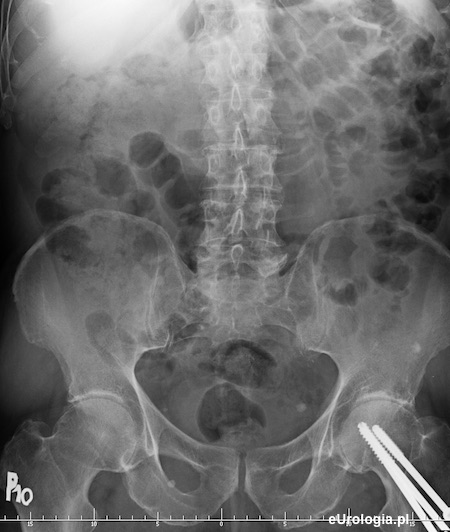

Urografia - kamica dolnego odcinka lewego moczowodu

Zdjęcie przeglądowe wykonywane przed podaniem kontrastu - cień wapienny w miednicy małej mogący być złogiem w dolnym odcinku lewego moczowodu